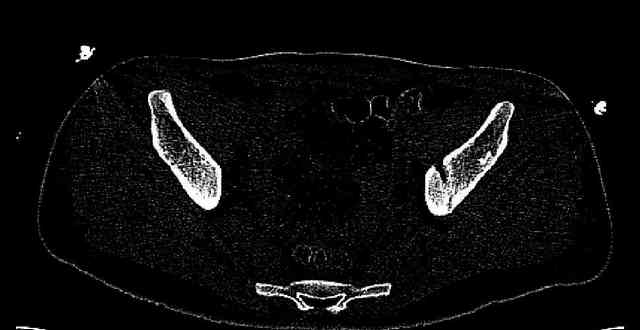

The joint is non-concentric as the head appears to be either "following the caudal segment", or the dome component is displaced from the tethered head... or so it seems... and he's young... so, many fracture surgeons would recommend reduction and fixation.

So we must decide preoperatively which part is the displaced segment?

It's difficult to know from these few selected images which component of the injury (was before and now) should be deemed the "soon to be mobile"

segment. It's my best guess that it is the caudal portion and there exists a healing fracture line somewhere thru the posterior column...one image

suggests it. If true, its early healing/union should be disrupted, and the resultant fragment mobility then allows accurate reduction.

Some more images. Does it help to guess which part of the acetabulum is displaced?

Normal appearing SI joints and a healed posterior column limb... my bet's on caudal segment displacement.